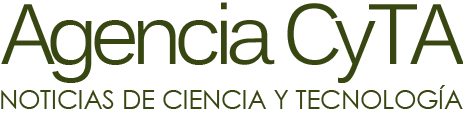

Ahora, un equipo liderado por la doctora María Bastianello, jefa de la Sección de Imágenes Moleculares y Terapias Metabólicas del Instituto Universitario CEMIC, logró resolver 11 casos dudosos mediante un tipo de tomografía, llamada “de emisión de positrones” o PET, que se usa, por ejemplo, para la detección de la progresión y el seguimiento del cáncer de próstata.

Bastianello y sus colegas advirtieron que el mismo radiofármaco que se inyecta para la identificación del tejido maligno (18F-Colina) en esa enfermedad “también es absorbido por tejidos celulares que se desarrollan por la presencia del hiperparatiroidismo”, por lo que puede ser detectado con el equipo de PET.

En diez de los once pacientes evaluados, informaron los especialistas, se confirmó el diagnóstico de hiperparatiroidismo. El trabajo recibió el primer premio en el congreso anual de la Asociación Argentina de Biología y Medicina Nuclear, que se celebró a fines del año pasado.